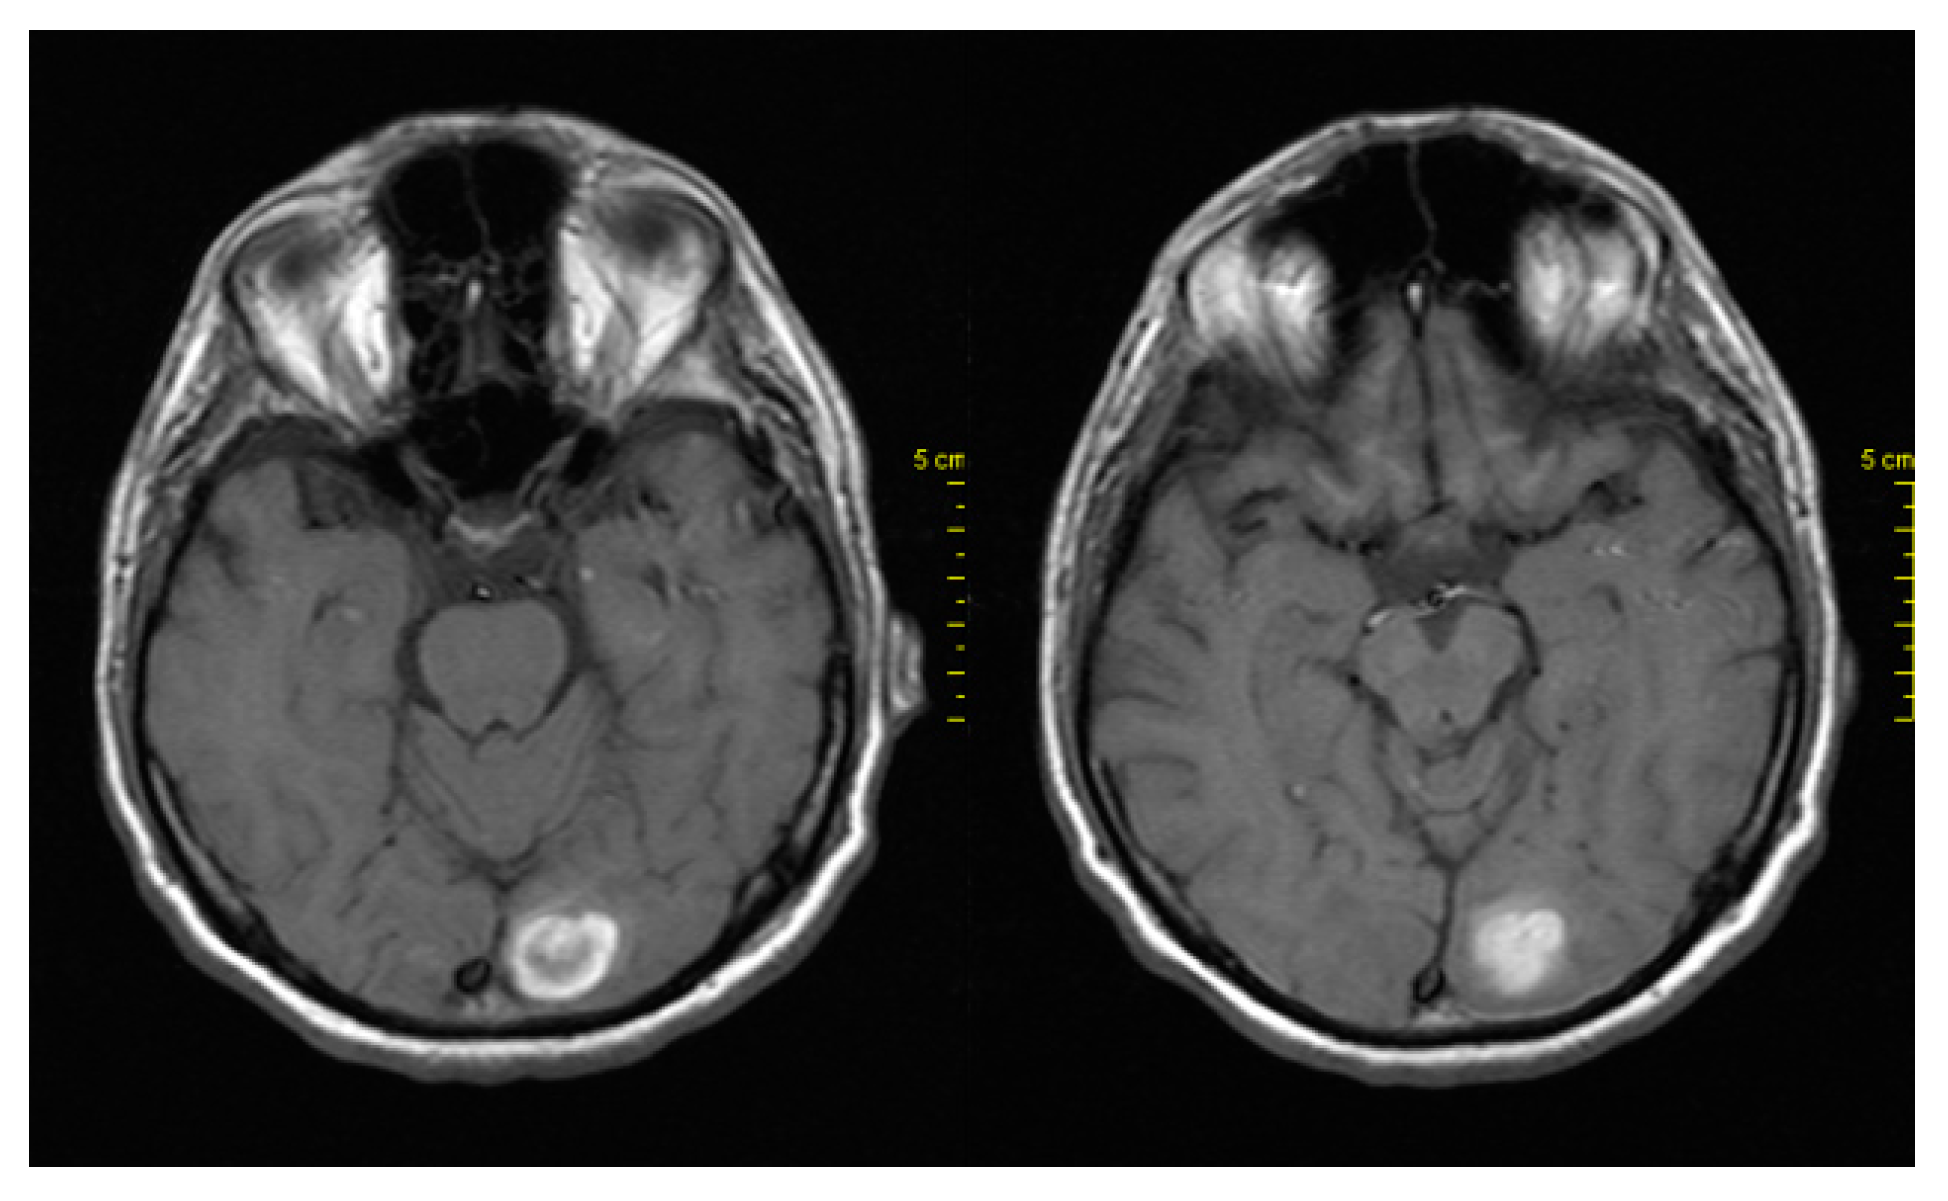

In April 2018, due to headache and dizziness, the patient underwent a neurological examination and brain imaging. Brain CT and MRI showed new brain metastases in the left occipital lobe (Figure 4). The next step was brain radiotherapy in May 2018, with 3000cGy to the whole brain and 600cGy boost. The patient subsequently continued receiving BRAFi + MEKi and showed clinical improvement. A CT scan of the brain performed after two months showed stability of the disease.

Figure 4. MRI showing brain metastases in the left occipital lobe.